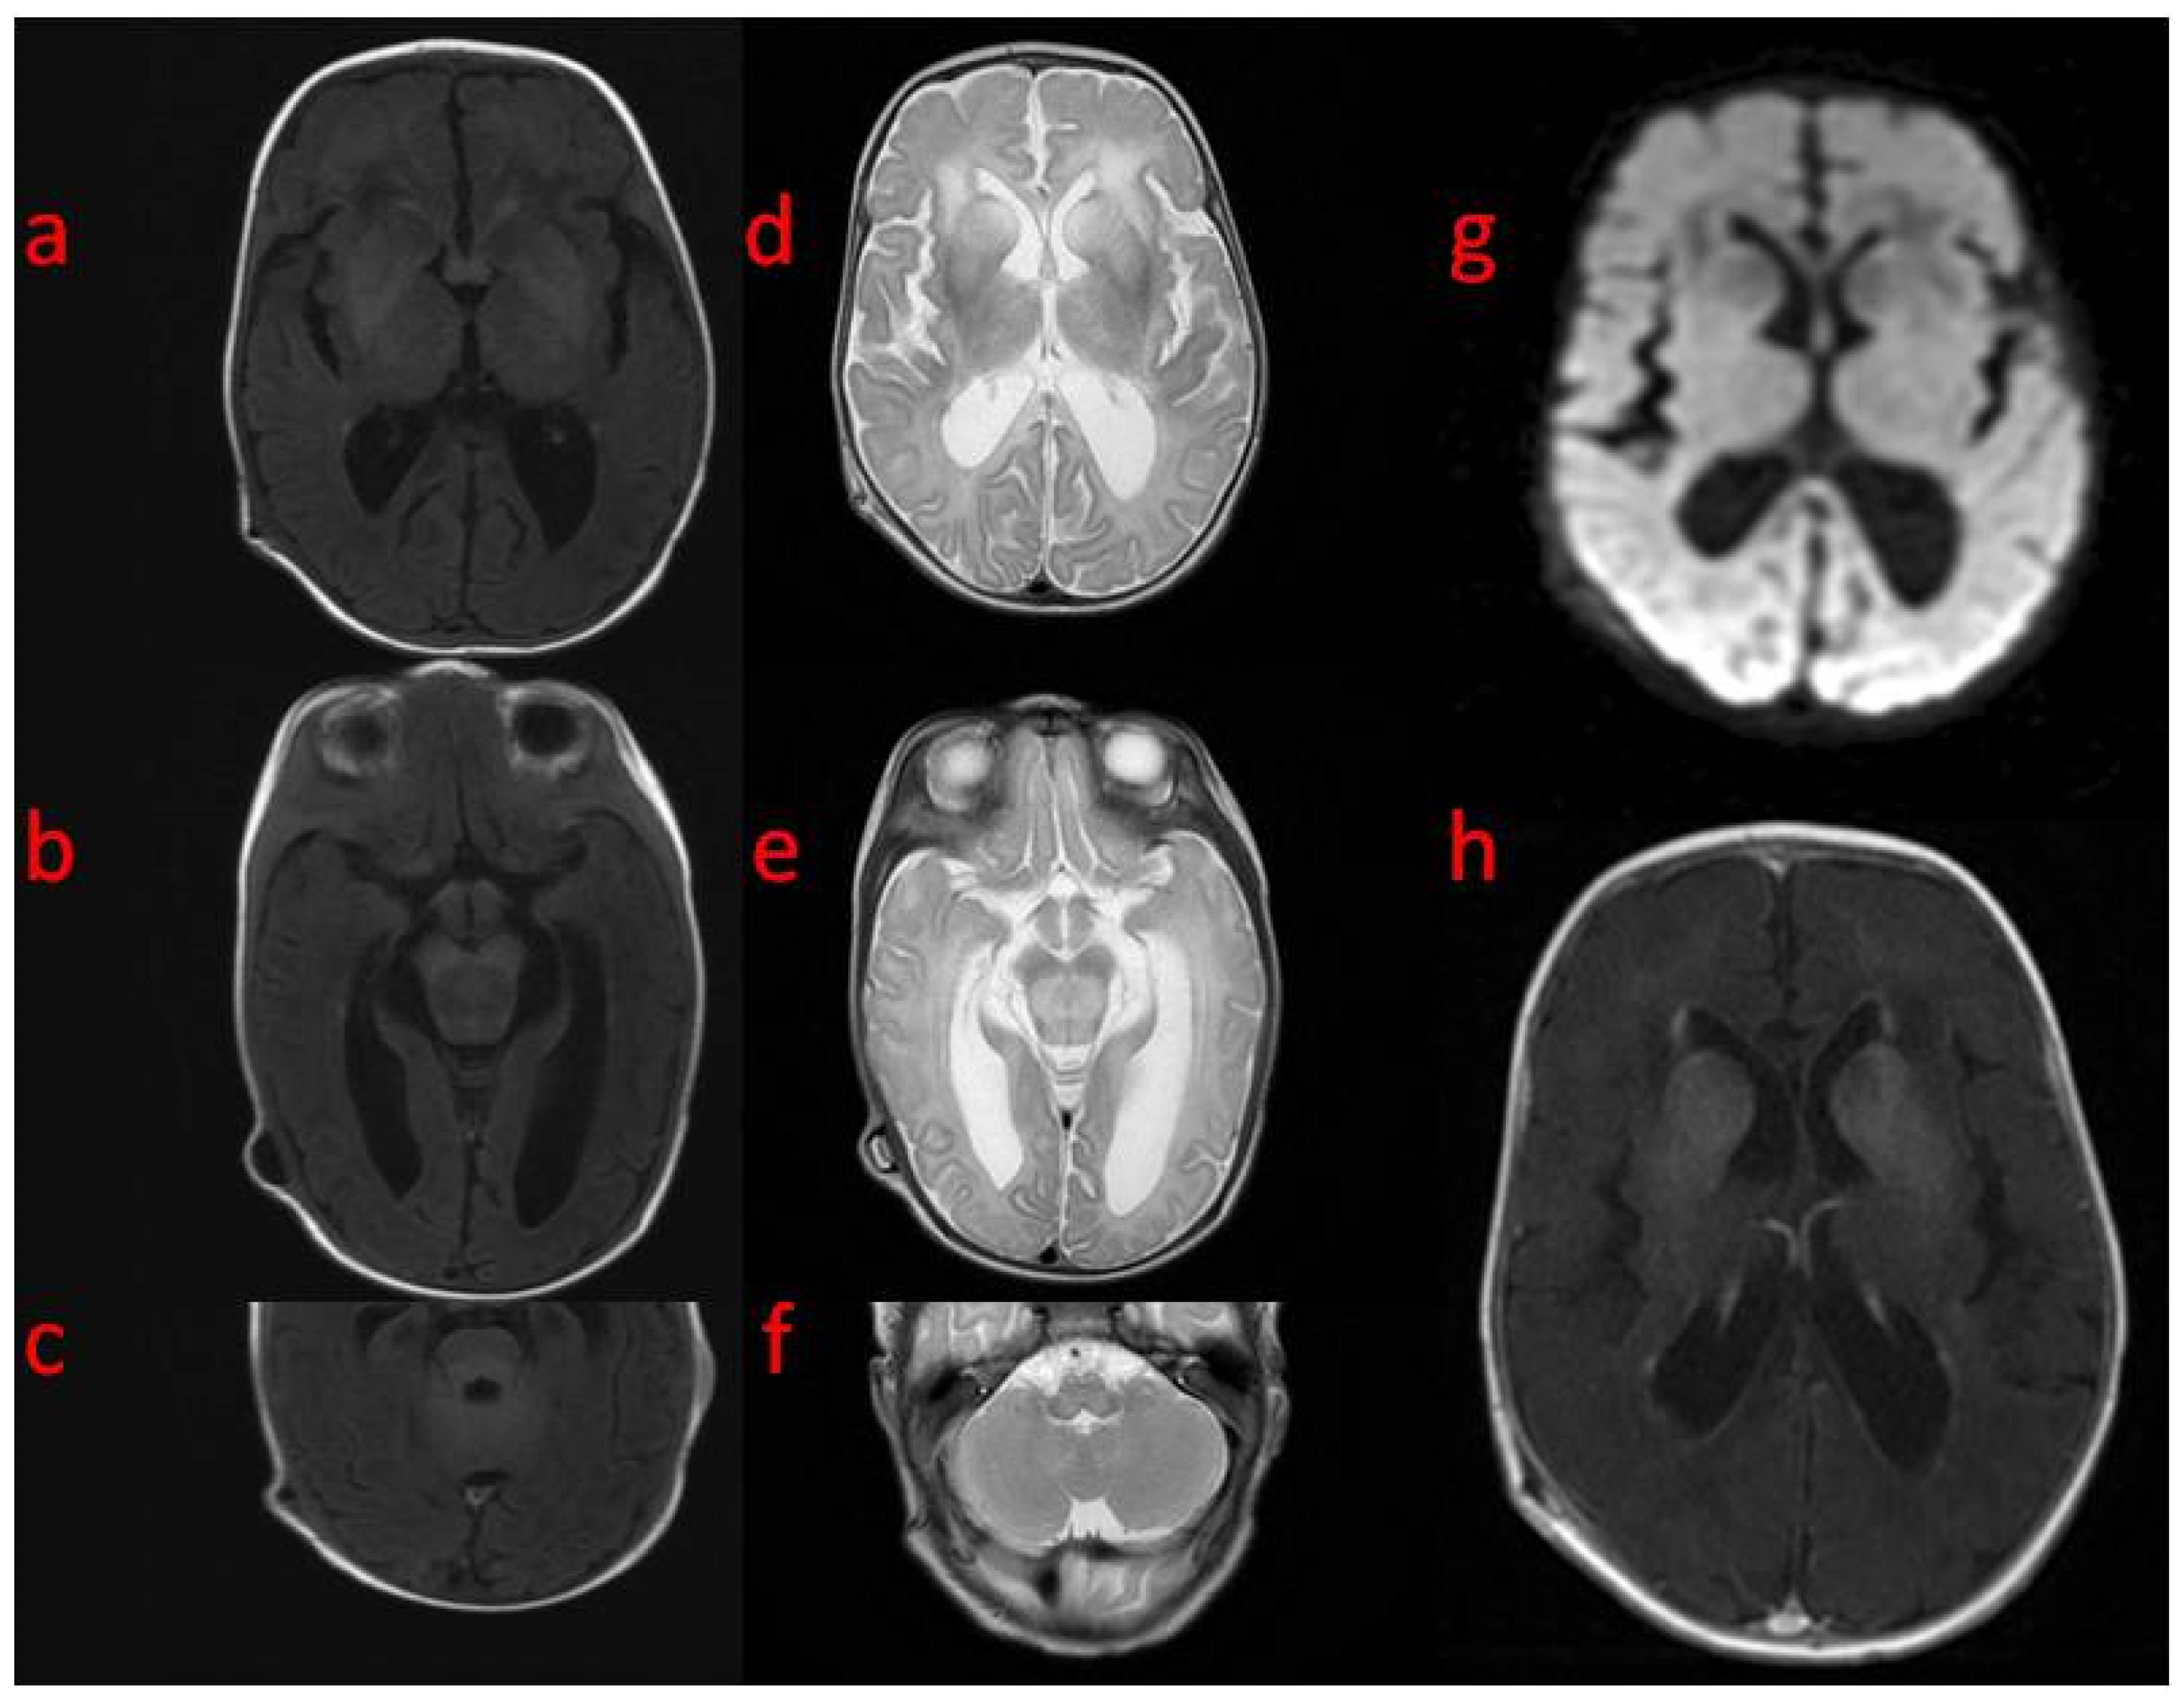

In the first weeks of life, the child presented with increasing apathy, severely limited spontaneous activity, and a lack of eye tracking. At the age of 5 weeks, a physical examination revealed the bulging frontal fontanelle and separation of the cranial sutures. A transfontanelle ultrasound examination showed a significantly enlarged supratentorial ventricular system with a ventricular index of 0.57 (N: 0.2–0.25). Signs of increased intracranial pressure led to ventriculoperitoneal shunt implantation. The surgery resulted in the resolution of the dehiscence of the sutures with limited improvement of the neurological state. MRI of the brain performed after neurosurgery revealed decreased T1 and increased T2 white matter signals in both hemispheres with frontal domination, midbrain, cortico-spinal tracts, and enlarged basal ganglia with heterogenous signals and enhancement. DWI (diffusion-weighted imaging) showed generalized abnormality and an even signal with increased diffusivity in the frontal white matter (Figure 1). In a 1-week follow-up, white matter signal changes were generalized, and symmetrical periventricular spaces in internal capsules were shown (Figure 2).

Figure 1. Brain MRI (ac) (5th week of life): axial T1 on the level of (a) basal ganglia, (b) midbrain, (c) pons with superior cerebellar peduncles with an abnormal signal in the frontal white matter, basal ganglia without signal changes in the pons and cerebellum (df): axial T2—(d) significantly increased frontal white matter and basal ganglia signal, enlarged caudate nuclei, (e) increased signal and volume in the midbrain, (f) increased signal in the oblongate medulla; (g) axial DWI—generalized even signal without differentiation except for increased diffusivity in the frontal white matter; (h) axial T1 post-contrast: enhancement of basal ganglia.